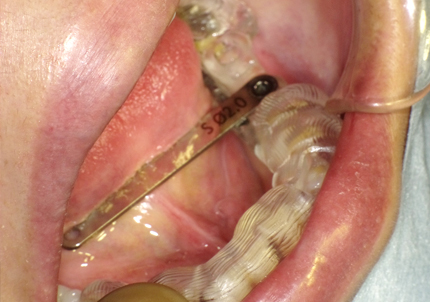

3.サージカルガイド(インプラント埋入用)作製(2019年3月)

7.サージカルガイドによるインプラント埋入手術

↑ Sirona Guide2使用